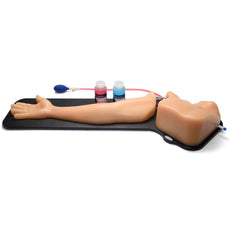

Foreign Body Identification Ultrasound Training Model, Leg

Foreign Body Identification Ultrasound Training Model, Leg

This CAE Blue Phantom foreign body single leg model is ideal for learning image acquisition and interpretation, and practicing the psychomotor skills necessary for ultrasound diagnosis, and ultrasound-guided procedures. Our patented Simulex tissue inserts allow learners to learn ultrasound system controls, positioning and moving the transducer and recognizing anatomy.

Foreign Bodies:- Metal projectile BBs

- Metal shrapnel fragments

- Wooden splinters

- Metal needles

- Large glass fragments

- Glass shards

Product Dimension and Weight:

- Dimension: 32” long x 8” wide x 8” high (81 cm x 20 cm x 20 cm)

- Weight: 25 lbs. (11.5 kg)